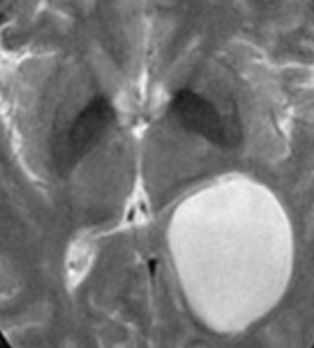

Субтенториальная эпидермоидная киста и арахноидальная киста полюса левой височной доли. КТ, аксиальный срез (а), МРТ, аксиальное Т2-ВИ (b) и аксиальное Т1-ВИ (с) после введения КС. Ни КТ, ни традиционные МР-изображения не позволяют четко дифференцировать эпиде моидные кисты от арахноидальных. Подобно кисте паутинной оболочки, эпидермоидная киста выглядит гиподенсной (а) или гиперинтенсивной (b) и гипоинтенсивной по отношению к паренхиме головного мозга (с) и не накапливает КС (с, стрелка). Однако МР-сигнал в эпидермоидной кисте неоднородный.